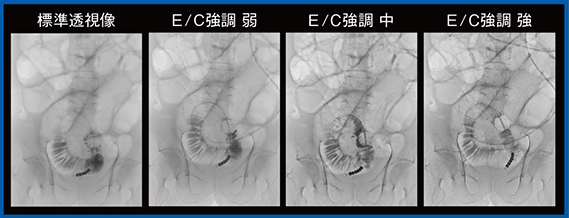

2.尿管ステント交換症例と造影症例

尿管ステント交換症例は,E/C強調の弱の評価が高く(図6),経イレウス管小腸造影検査では,E/C強調の中または強で造影剤の流れが明瞭に確認できた(図7)。

図7 経イレウス管小腸造影(Accent適用)